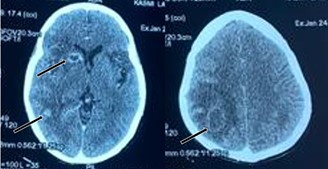

A 44-year-old woman, with a history of miscarriage in 2019 and uninvestigated uterine bleeding since october 2022. She was admitted on December 2022, due to left hemiplegia with facial palsy and language disturbances. These symptoms were preceded by behavioral changes, characterized by agitation and incoherent speech, developing progressively over the preceding month. Physical exam revealed confusion and left hemiplegia. Brain MRI revealed multiple bilateral ischemic strokes involving carotid and vertebrobasilar territories (Figure 1). Due to clinical worsening on the second day of hospitalization, a cerebral CT scan showed a new ischemic stroke of the right middle cerebral artery (Figure 2).

Figure 2: Brain CT scan revealing a new contralateral ischemic stroke: Right Sylvian ischemic stroke with mass effect.

Meanwhile, the β-hCG levels continued to rise (66,019 mIU/mL). The clinical course was marked by the emergence of cerebral metastases, and the patient death one month after the vascular event (Figure 3, 4).

Figure 4: Brain CT with contrast injection showing multiple brain metastases.